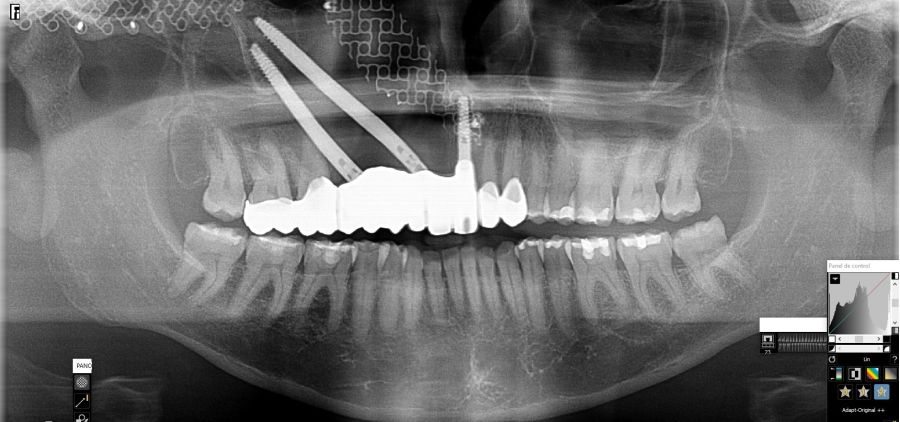

Bajo anestesia general, se realizó la resección quirúrgica junto con la fijación de dos placas preformadas y colocación simultánea de dos implantes cigomáticos y un implante endoóseo en posición del 2.1 (Figuras 5 y 6). Debido a la presencia de márgenes quirúrgicos comprometidos en el informe anatomopatológico, se indicó la administración de radioterapia adyuvante. Por este motivo, se decidió realizar un puente provisional dentosoportado de 1.7 a 2.3 (Figura 7) para mejorar la situación estética y funcional de la paciente durante todo el proceso y evitar un colapso de los tejidos blandos por la radioterapia. Para ello, se tallaron los molares (1.7, 1.6) e incisivo lateral y canino (2.2, 2.3), y se fabricó un puente fresado en polimetilmetacrilato (PMMA) con refuerzo metálico (Figuras 8 y 9).

Al mes de la intervención, la paciente comenzó con la radioterapia. El protocolo de radioterapia adyuvante fueron 30 sesiones.

Una vez finalizada la radioterapia, la paciente se encontraba libre de enfermedad. Por lo que se procedió a la restauración definitiva implantosoportada. Tras la segunda fase, se colocaron dos pilares transepiteliales Multiunit Ò rectos y un pilar Multunit Ò angulado de 17º (Figura 10).

Finalizado el tratamiento oncológico y confirmada la ausencia de enfermedad activa, se procedió a la segunda fase quirúrgica con la colocación de pilares transepiteliales Multiunit®. La integración de los implantes cigomáticos y del implante endoóseo fue satisfactoria, observándose estabilidad clínica y ausencia de signos de periimplantitis.

En el seguimiento a 4 años tras la colocación de la prótesis definitiva, no se observaron complicaciones mecánicas ni biológicas. La paciente continúa libre de enfermedad y con una correcta adaptación al tratamiento rehabilitador implantosoportado (Figura 18).